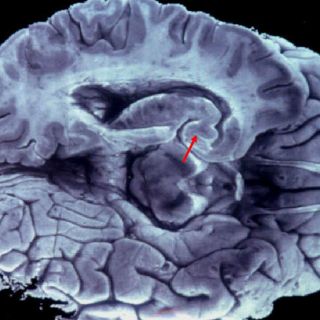

Liu Jiayu, de la sureña provincia de Hunan, sufrió un accidente cerebrovascular isquémico causado por una obstrucción en los vasos sanguíneos, lo cual le causó daños en la parte del cerebro relacionada con el lenguaje materno, informaron los neurólogos que la atienden.

Explican que la información relacionada con la lengua materna de una persona se almacena en el lado izquierdo del cerebro, mientras que la capacidad de aprender y hablar un segundo idioma en el lado derecho.

Los expertos dicen que la lengua china es compleja y requiere el uso de ambas partes del cerebro, mientras que el idioma inglés sólo utiliza uno de los lados, lo cual explicaría la condición de la ex profesora.